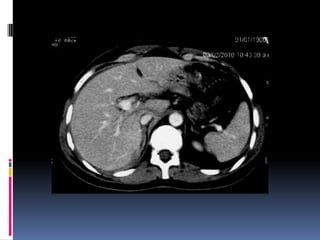

¿LÍQUIDO LIBRE HIPERDENSO? Diagnóstico: RUPTURA VESICAL